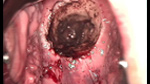

婦科leep錐切手術(shù) CIN2-3

• CIN 2-3CIN 2-3